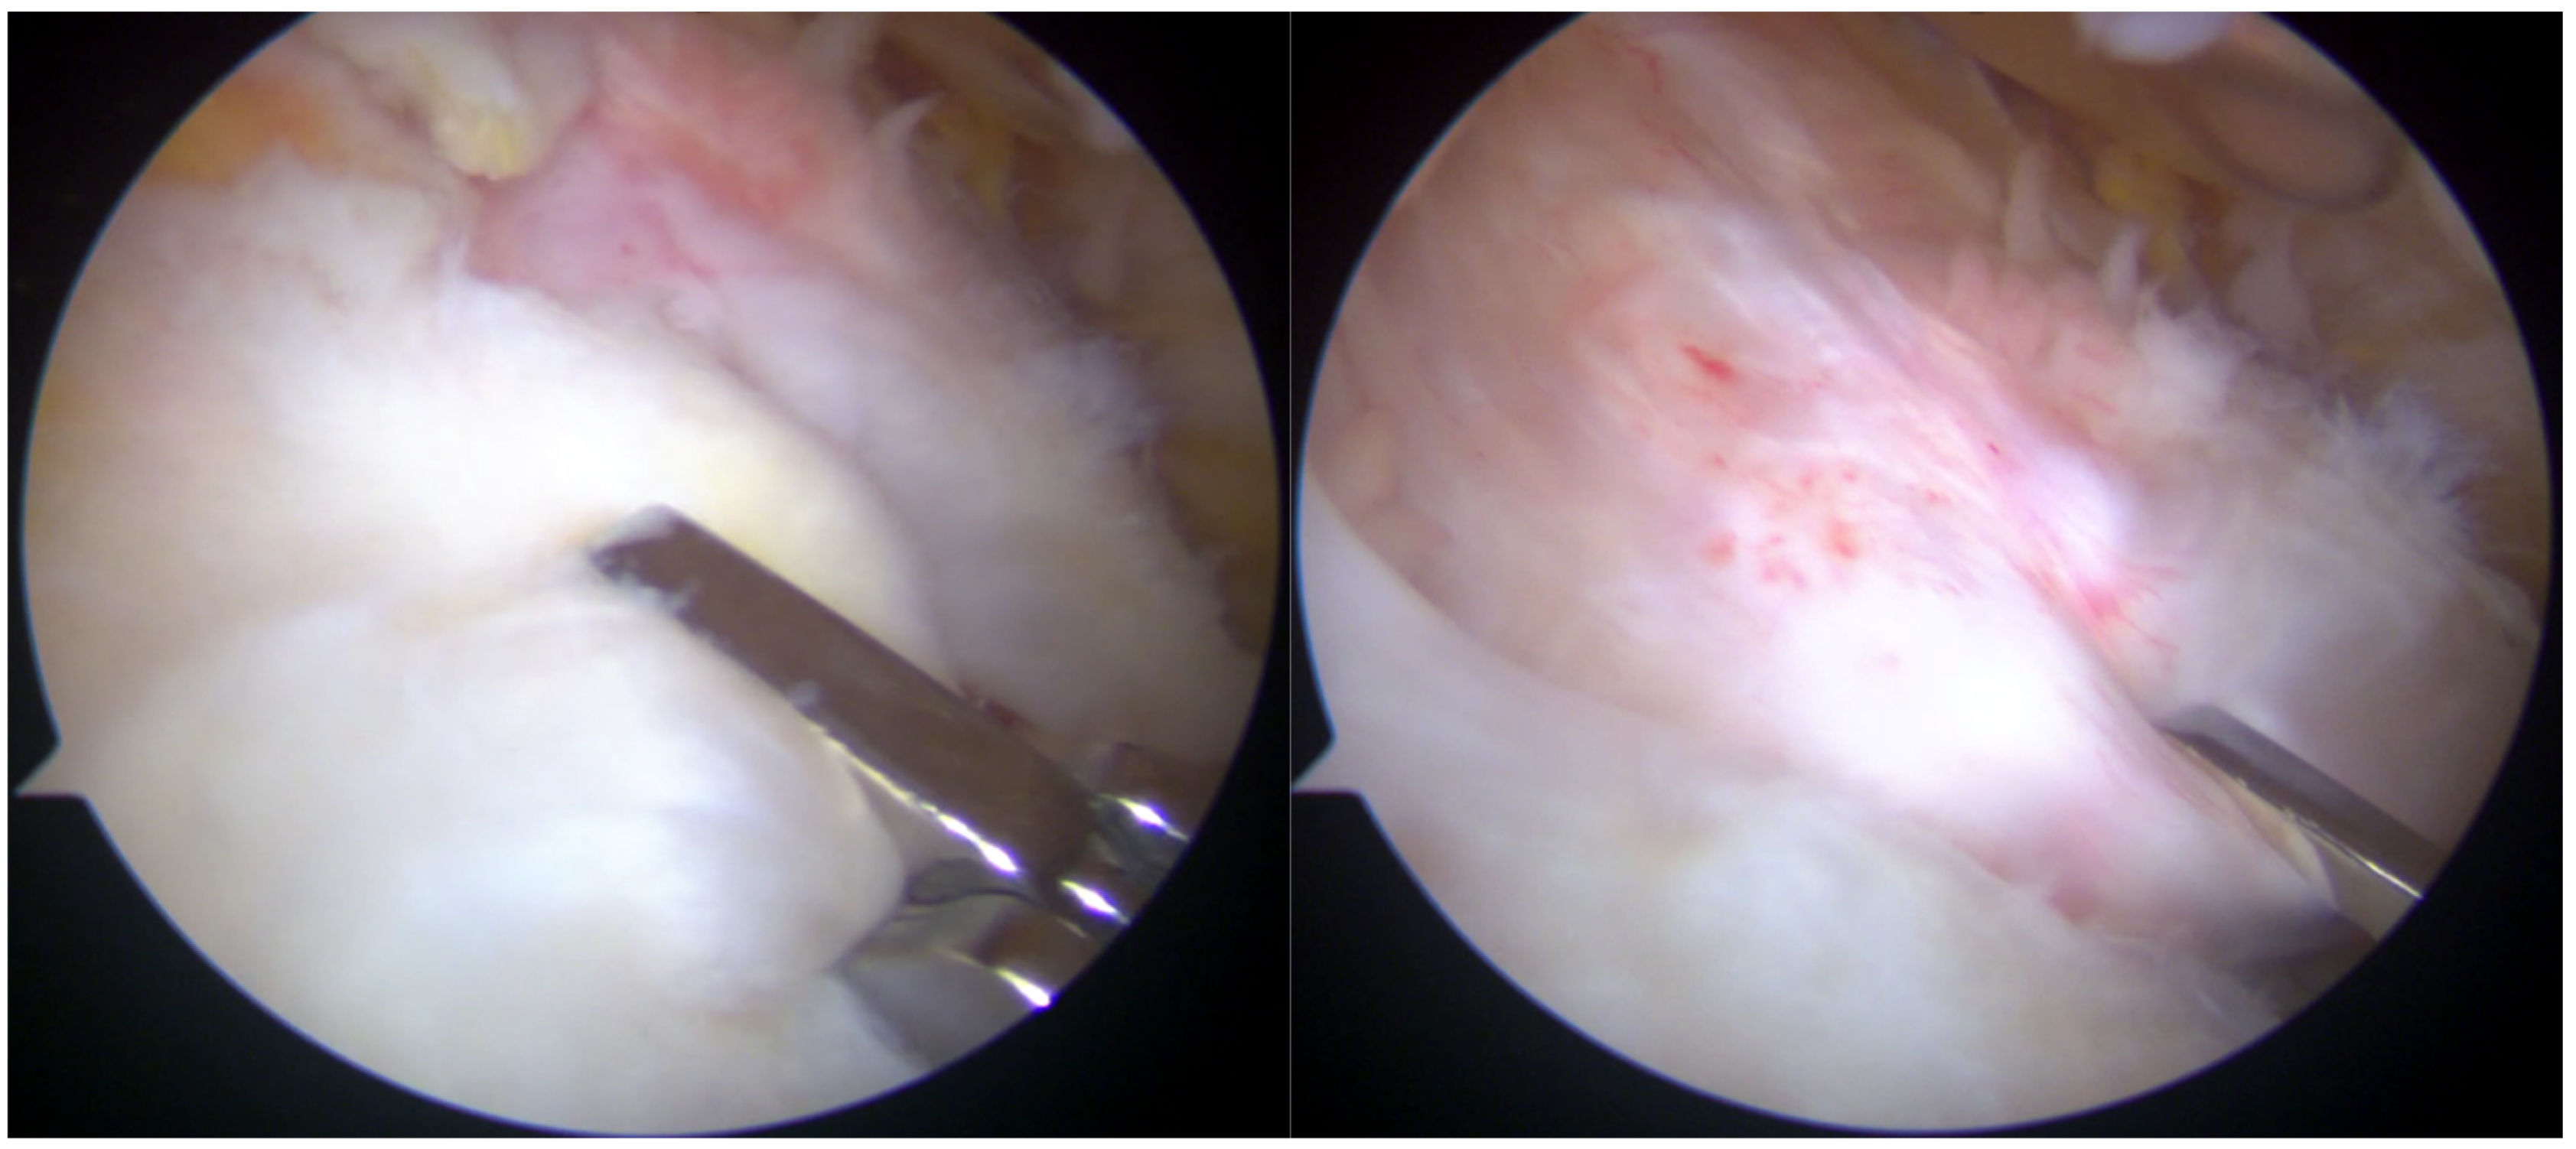

Arthroscopic visualization revealed multiple layers of the rotator cuff. Sheets 2 and 3 of the infraspinatus tendons were identifiable, while only sheet 3 of the supraspinatus tendon was visible, with sheet 2 absent (Figure 3). The mobilization of the rotator cuff confirmed that restoration to the footprint could be achieved without excessive tension (Figure 4).

Figure 3.

Subacromial view demonstrating full-thickness rotator cuff tear involving the supraspinatus (S) and infraspinatus (I) tendons. Only sheet 2 of the supraspinatus tendon is visible, while both sheets 2 and 3 of the infraspinatus tendon are present.

Figure 4.

Reduction maneuvers demonstrated the ability to reposition sheet 3 of the supraspinatus tendon (right image) and sheets 2 and 3 of the infraspinatus tendon (left image) back to their native footprint.

The lesion involved a full-thickness tear affecting both the supraspinatus and infraspinatus tendons, with separation into superficial bursal and deep articular layers. The layers exhibited differential retraction and elasticity; the superficial layers were more retracted compared to the deep layers. The complete reduction of the infraspinatus tendon was achieved, whereas only the deep layer of the supraspinatus tendon could be restored to the footprint due to the excessive retraction and stiffness of the superficial layer. Given the chronicity and severity of the tear, a complete anatomical repair was deemed unattainable. The frayed edges of the tendon were meticulously debrided to prepare for repair. Two suture anchors (Q-FIX 2.8 mm, Smith and Nephew, London, UK) were employed to secure the torn tendon back to its native humeral attachment using a single-row repair technique.